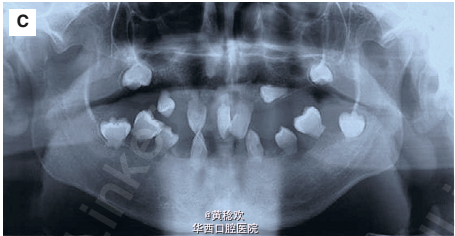

牙本质发育不良是一种罕见的常染色体显性遗传疾病(发病率1:100000),牙本质形成受阻,在临床上通常表现为临床牙冠正常,但通过放射检查可见牙根形态不良甚至没有牙根,无髓室腔,根周有无任何诱因的透射影。牙本质发育不良可分为I型和II型,前者更常见,表现为有乳牙和恒牙,牙冠正常,但牙根退化或无牙根,在牙釉质牙本质界可见一水平的放射投射影线,根尖周有透射影或囊肿。II型特点为牙根形态轮廓正常,部分牙髓闭塞,不定形的牙本质可形成髓石,长梗漏斗样牙髓室腔,线状根管,通常无根尖周透射影。因为牙齿缺乏正常牙根形态,很难通过临床上常规的操作将其移动排齐。 今日为大家分享一例因为牙本质发育不良I型的病人行全口种植修复的案例。